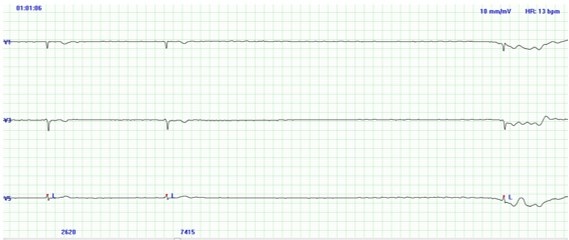

Η άλλη ασθενής, γυναίκα 83 ετών, επίσης με ιστορικό υπέρτασης, έπρεπε να υποβληθεί σε μία μικρή γυναικολογικής φύσης επέμβαση. Στο ηλεκτροκαρδιογράφημα που της έγινε πριν την επέμβαση, διαγνώστηκε με κολπική μαρμαρυγή (αρρυθμία η οποία πολύ συχνά προκαλείται από υπέρταση), με πολύ αργό ρυθμό παλμών (38 παλμοί το λεπτό). Οπότε η επέμβαση έπρεπε να αναβληθεί ώστε να εξετασθεί η καρδιά της περαιτέρω. «Δεν αισθανόμουν την αρρυθμία της καρδιάς μου, το μόνο που αισθανόμουν τελευταία, ήταν αρκετή κούραση» λέει η ίδια. Το Triplex καρδιάς έδειξε την καρδιά και τις καρδιακές βαλβίδες σε καλή κατάσταση, αλλά το 24ωρο Holter Ρυθμού έδειξε πολλές παύσεις – μέχρι και μέγιστη παύση των 7 δευτερολέπτων (βλέπε φωτο & στοιχεία ασθενή παρακάτω).

Γυναίκα Ασθενής: κολπική μαρμαρυγή με 38 παλμοί το λεπτό και Παύση 7 δευτερολέπτων, στο 24ωρο Holter Ρυθμού